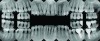

A series of full-mouth diagnostic radiographs that visualize each tooth or implant are critical as a baseline (Figure 11). The frequency and type of radiographs needed at maintenance depends on the severity of periodontal disease, as well as the extent of restorative treatment and caries susceptibility. With more advanced periodontal disease and restorative concerns, more frequent radiographs may be indicated. Vertical bitewing radiographs provide a better view of osseous crest levels and should be considered over horizontal bitewing radiographs for periodontal cases (Figure 12).

Fig 11. Full-mouth series of radiographs.

Figure 11

Fig 12. Vertical bitewing radiographs.

Figure 12